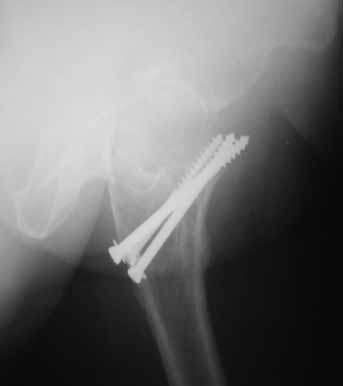

На консультации вот такие снимки. Больная 72 года. упала в быту 26 декабря 2010г.

Оперирована 30 декабря 2010г. в одном из стационаров края. Назначили дополнительное обследование, а пока хотелось-бы услышать мнение по-поводу возможностей сохранения головки. Больная из льготного контингента, т.е. современные констукции и эндопротез маловероятны.

Обычное после фиксации перелома шейки варусное смещение по разным публикациям встречается от 15-24%. В оценке состояния пожилых больных применяется коэффициент (ADL) Activities of daily living. В зависимости от базового ADL, т.е. до переломного состояния планируется лечение. Кроме того, возраст играет важную роль, и не всегда функциональное состояние совпадает с истинным возрастом. Поэтому каждый случай после 60 лет рассматривается отдельно.